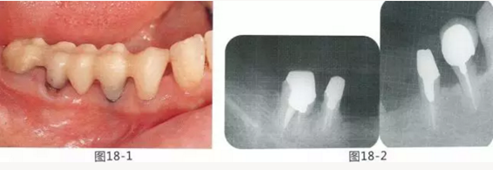

圖18-1 右上4,5,6,6,7部位,初期治療結束時牙齦的狀態(tài)。

圖18-2 手術前同部位的口腔X光片。

圖18-4 去除臨時修復體后的頰側面照。在手術前去除右下5,6,7的金屬樁可以使手術更為方便。右下5,6部位基本看不到角化牙齦。

圖18-5 同部位的舌側面照片。角化牙齦較少,將牙槽嵴頂預測切開的話很有可能會沒有任何角化牙齦。